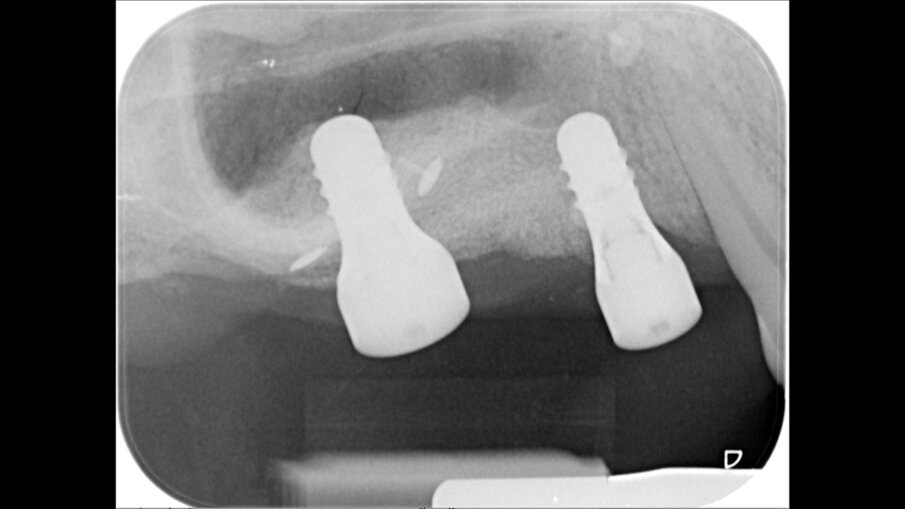

A distanza di 6 mesi, previa acquisizione di una CBCT (Figg. 8-10), si procede con il rientro chirurgico nella sede ricostruita (Fig. 11). Scheletrizzato il mascellare ricostruito, si riscontra una parziale risoluzione del difetto verticale in sede 1.5 e il ripristino di volumi ossei idonei all’inserimento di impianti in posizione protesicamente guidata in sede 1.4 ed 1.6. Durante la preparazione dei letti implantari, si esegue il prelievo di due carote ossee mediante fresa trephine da 3.3 mm. Segue quindi l’inserimento di due impianti Tissue Level SP 4.1 x 8 mm (Straumann) e l’adozione di un protocollo di guarigione sommerso (Figg. 12, 13).

Fig. 12 - Prelievi bioptici ed inserimento implantare.

Fig. 13 - Chiusura per prima intenzione e sommersione impianti.